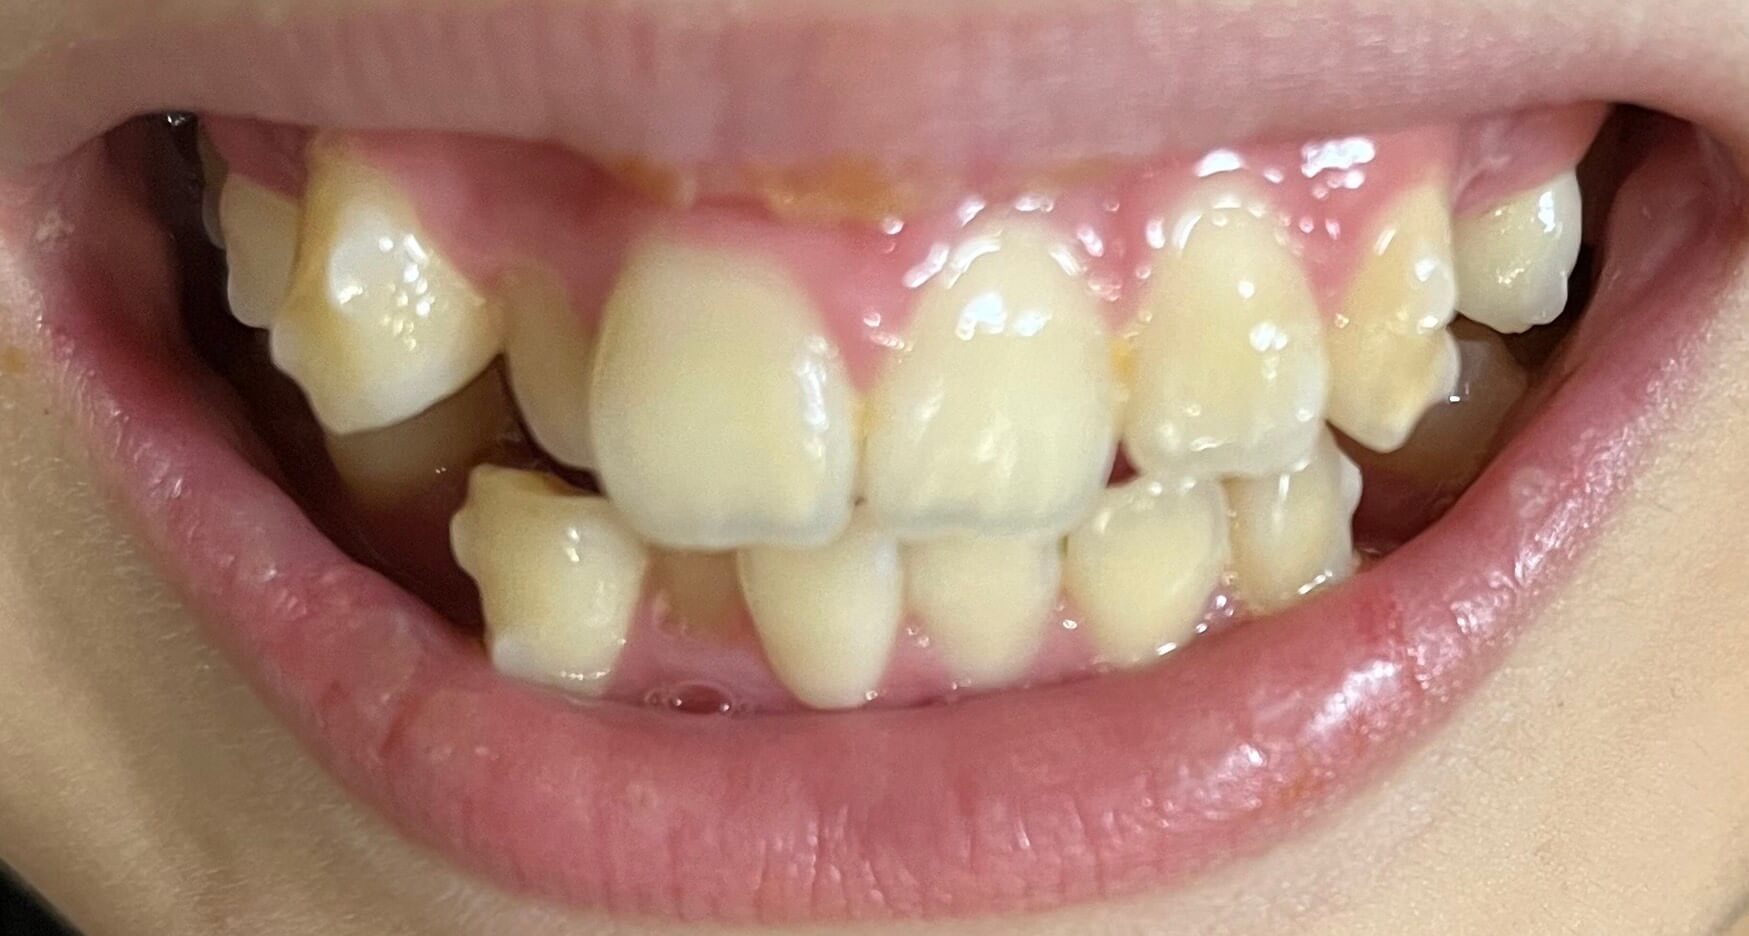

| 主訴 | 叢生が気になる |

| 治療期間・回数 | 1年 |

| 費用 | 935,000円 |

| 治療期間・回数 | 2年 |

| 治療期間・回数 | 1年9ヶ月 |

| 費用 | 1,011,000円 |

| 主訴 | 叢生が気になる・前歯に埋伏歯がある |

| 治療期間・回数 | 6ヶ月 |

| 上顎の左側3番が埋伏していたため、上顎左右の3番および親知らずを抜歯し、矯正治療を行いました。 治療開始からおよそ6ヶ月で歯列が整い、審美的にも機能的にも良好な結果が得られた症例です。 |